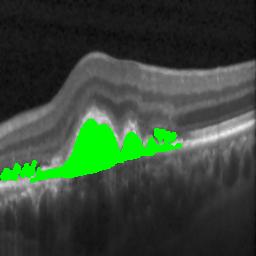

The qualitative results of the proposed system is shown in the Fig. 3. The detection task is evaluated using Area Under the Curve(AUC) metric and the segmentation task is evaluated using Dice Coefficient(DC) metric and the results are presented in Table1

| (a) De-noised OCT slice | (b)Predicted fluid region | (c)Manual fluid segmentation |

| (d) De-noised OCT slice | (e)Predicted fluid region | (f)Manual fluid segmentation |

| (g) De-noised OCT slice | (h)Predicted fluid region | (i)Manual fluid segmentation |

| (j) De-noised OCT slice | (k)Predicted fluid region | (l)Manual fluid segmentation |

| (m) De-noised OCT slice | (n)Predicted fluid region | (o)Manual fluid segmentation |